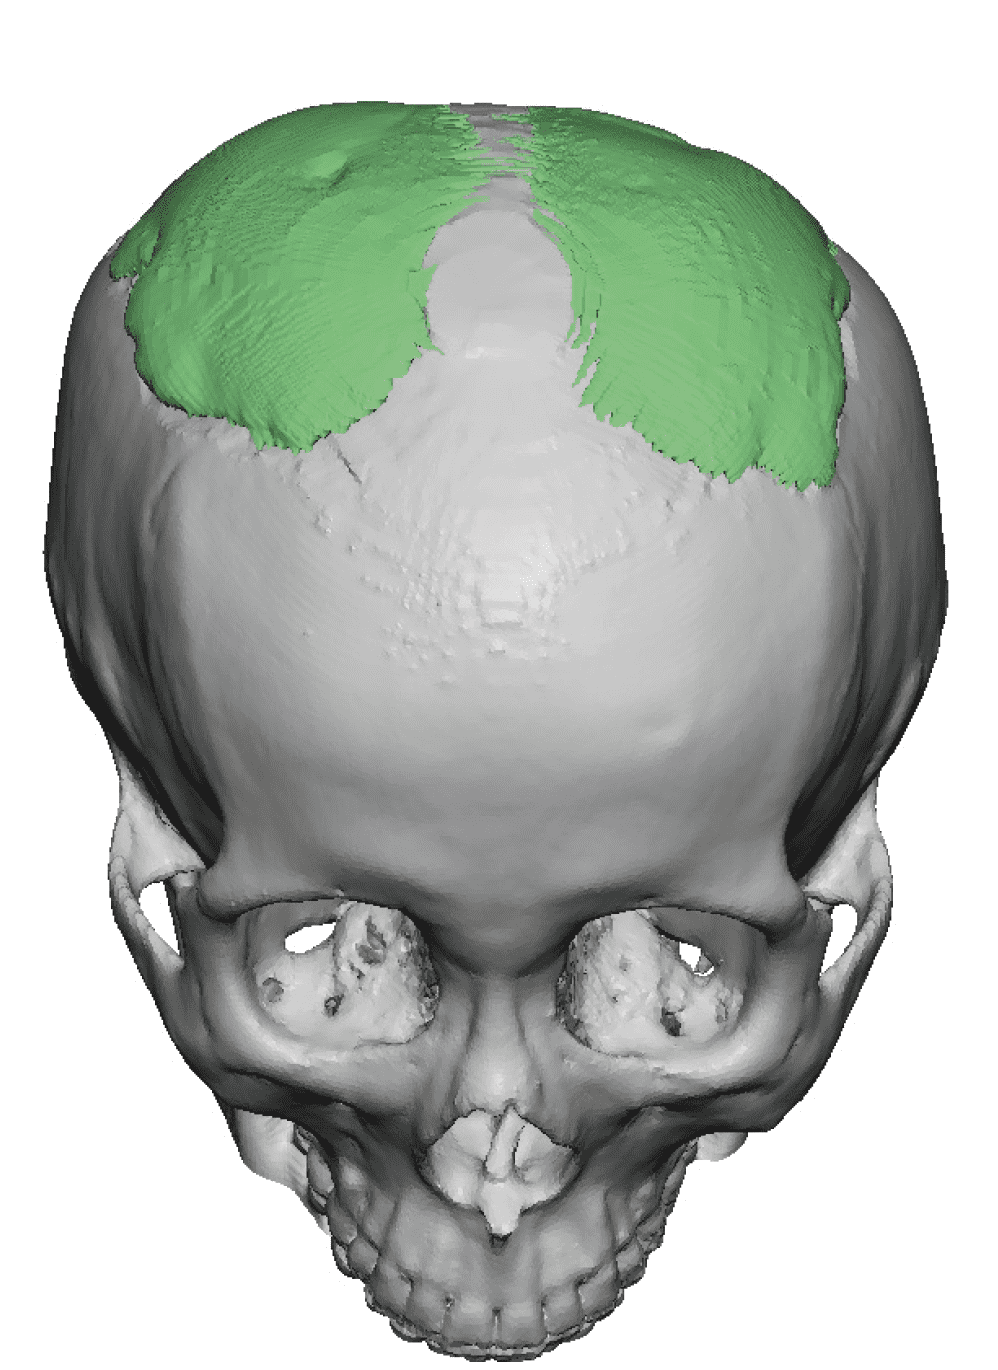

Desire for change of head shape from front view form an inverted V shape to a rounder and wider head shape.

Placement of custom extended forehead-temporal implants through incisions in the crease behind the ear. (he had a prior back of head skull implant which is green in the implant designs and which the head widening implants partially covered it)

Desire for change of head shape from front view form an inverted V shape to a rounder and wider head shape.

Placement of custom extended forehead-temporal implants through incisions in the crease behind the ear. (he had a prior back of head skull implant which is green in the implant designs and which the head widening implants partially covered it)